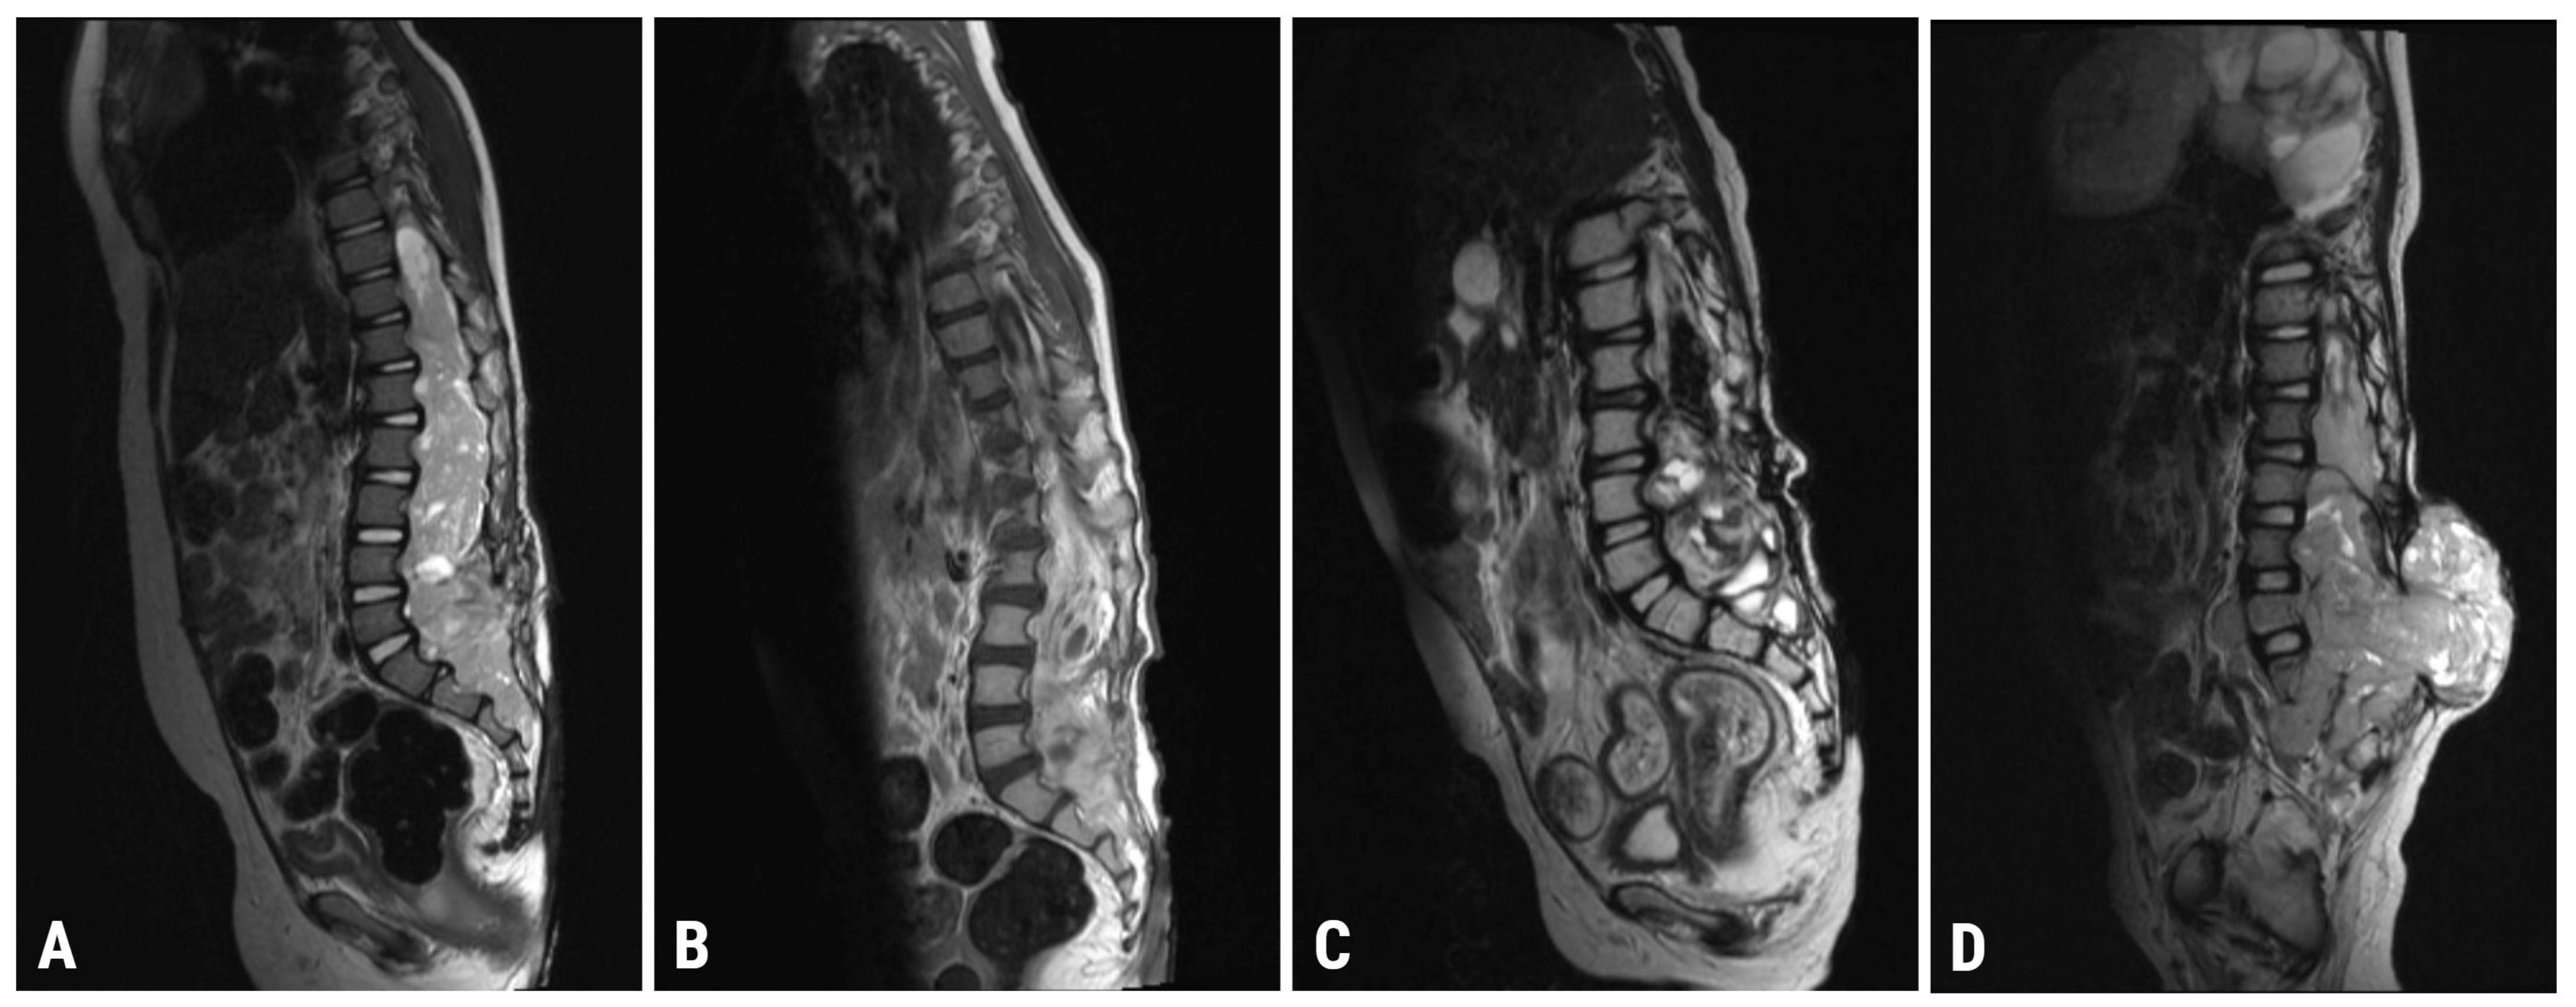

| 8 January 2021 | Spinal MRI (T9-S4 mass: 39 × 36 × 205 mm; & C1-C2 mass: 7.4 × 6.2 mm; Figure 1A) Brain MRI (leptomeningeal metastasis of the left temporal lobe: 25 × 5.5 mm) |

| 4 May 2021 | Spinal MRI (T9-S4 mass: 38 × 32 × 193 mm; & C1-C2 mass: 7 × 3 mm; Figure 1B) Brain MRI (unchanged leptomeningeal metastasis of the left temporal lobe: 25 × 5.5 mm in size) |

| 22 October 2021 | Spinal MRI (T9-S4: 36 × 32 × 190 mm; & C1-C2 mass: 7 × 3 mm; Figure 1C) Brain MRI (leptomeningeal metastasis of the left temporal lobe: 20 × 4 mm) |

| 6 April 2022 | Spinal MRI (T11-S2 mass: 76 × 75 × 195 mm; & C1-C2 mass: 7 × 5 mm; Figure 1D) Brain MRI (leptomeningeal metastasis of the left temporal lobe: 17 × 6 mm in size) |